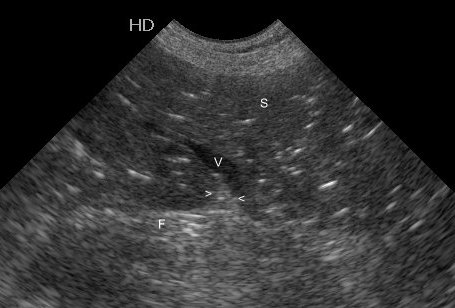

More on the diagnosis of pneumonia using ultrasound

This is a really good recent paper on the subject from human medicine: Emerg Med J. 2012 Jan;29(1):19-23. doi: 10.1136/emj.2010.101584. Epub 2010 Oct 28. Lung ultrasound is an accurate diagnostic tool for the diagnosis of pneumonia in the emergency department. Cortellaro F1, Colombo S, Coen D, Duca PG. In summary these authors found that, in … Continue reading